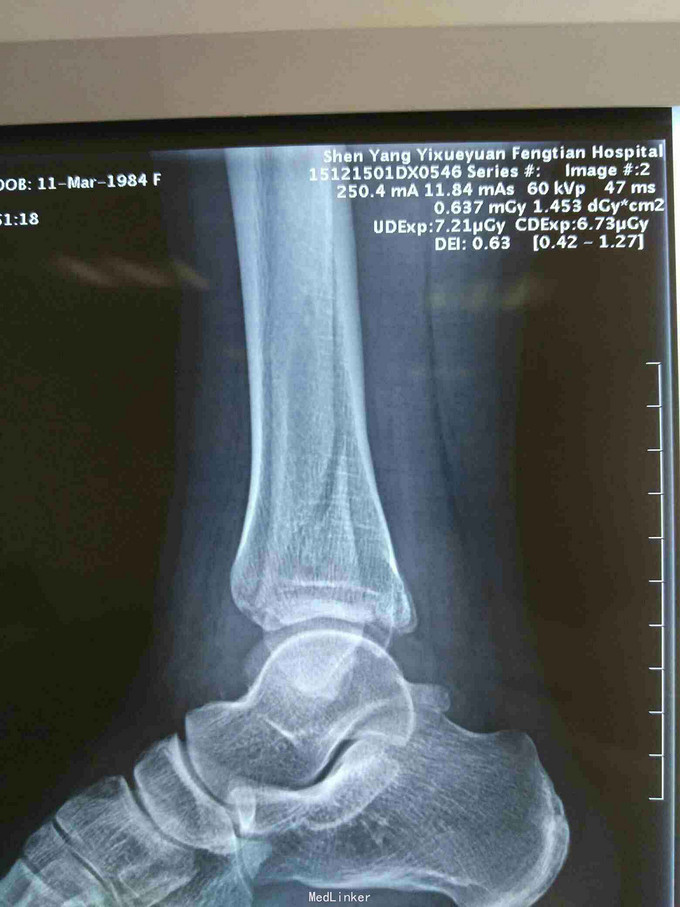

主诉:右踝外伤后肿痛,畸形,活动受限1天。 现病史:患者于2015年12月15号扭伤右踝后肿痛,畸形,活动受限,休息后未见好转,于次日来诊我院,经门诊拍片,阅片及查体后以“右三踝骨折”为诊断收入院。

查体:右踝局部皮肤完整,无破溃,右踝局部肿胀明显,畸形明显,可见皮下淤血,呈青紫色,右踝环形压痛阳性,可触及骨察音及骨察感,异常活动存在,右踝关节活动受限,末梢各趾活动自如,足背动脉清。 辅助检查:大致正常。

诊断:右三踝骨折 治疗:患者入院后完善检查,对症治疗,于2015年12月25日行手术治疗。